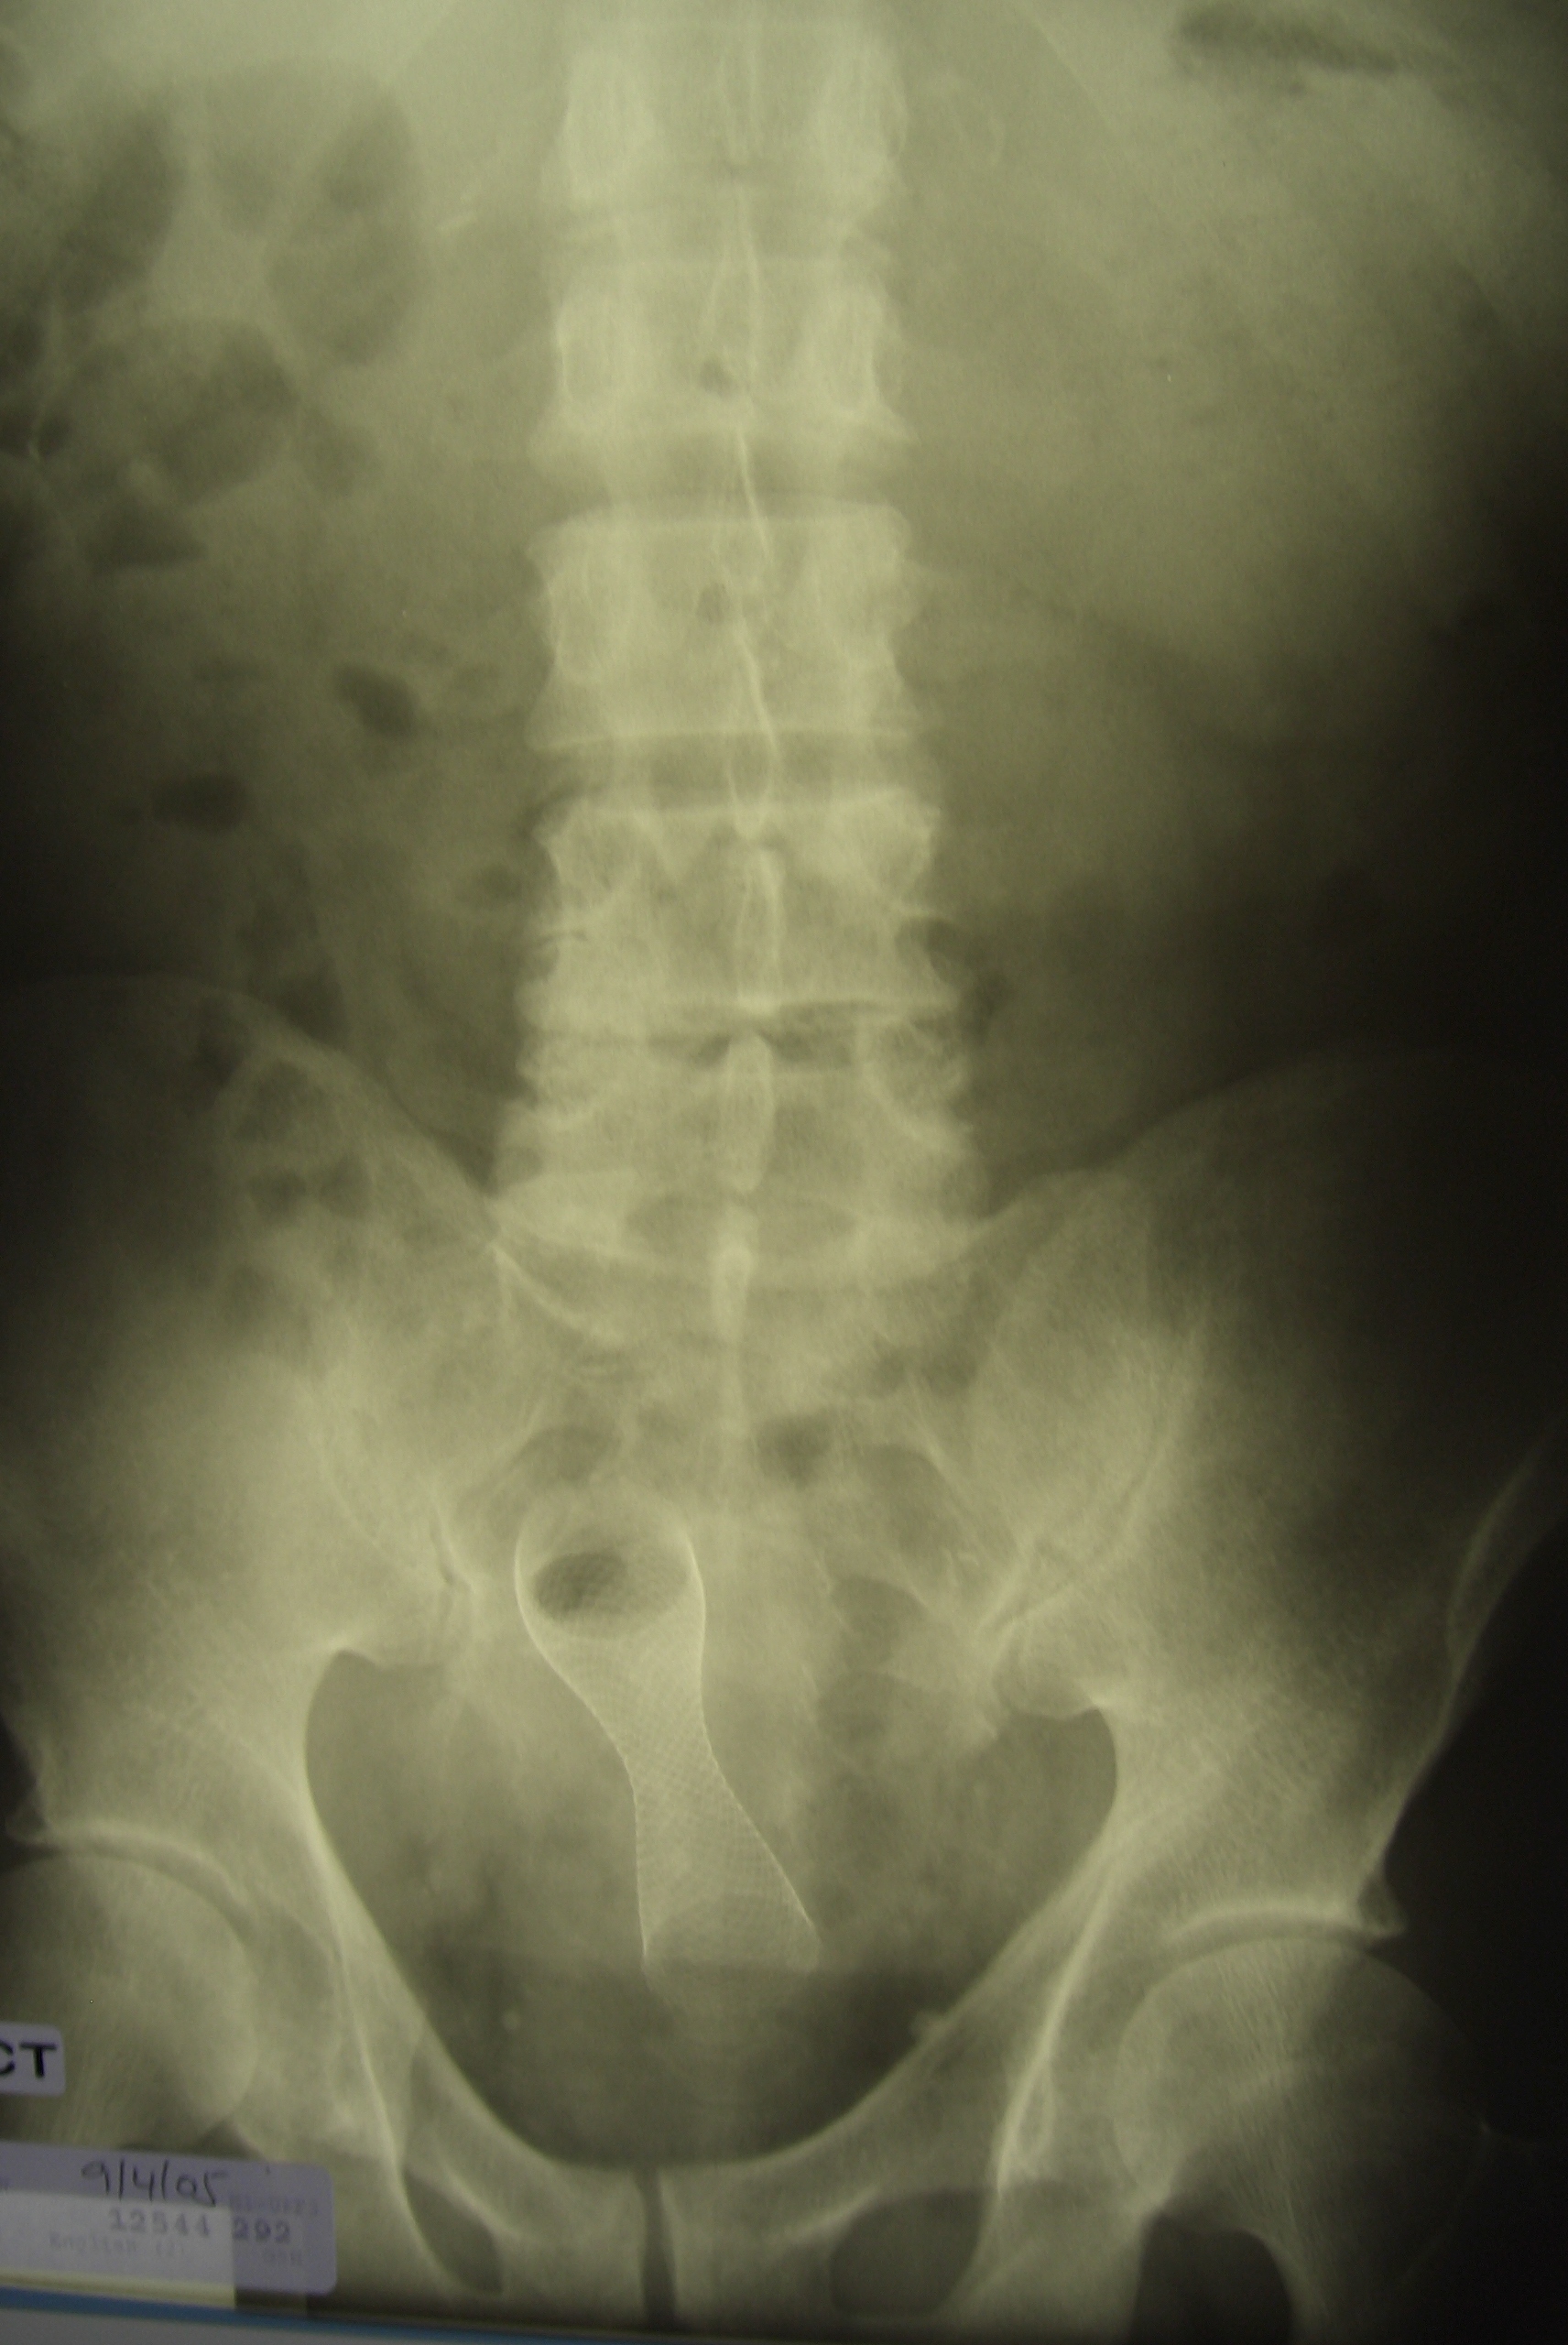

Colorectal cancer affects approximately 1:20 of the population and in South Africa is largely managed by general surgeons. Management of this disease has undergone very significant changes over the last two decades. Until very recently, only two academic general surgery departments included a specialist colorectal unit, and this remains so in the majority of our universities. This has resulted in a generation of surgical graduates who are unfamiliar with, and unskilled in current best management practices for this disease. Rectal cancer is particular challenging and attracts extremely high morbidity and mortality, with poor oncological outcomes. Repeatedly, outcome has been shown to be worse in the hands of generalists, rather than specialist colorectal surgeons, of whom there are very few in the country. This review presents the most important advances of the last 20 years and highlights current controversies and frontiers.